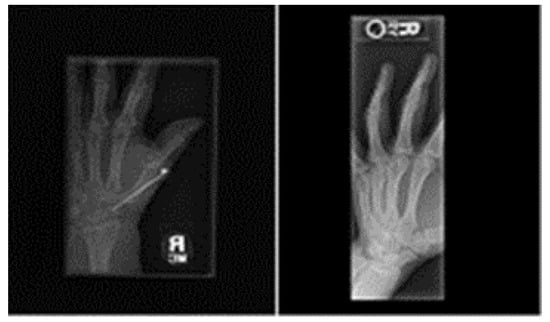

3.1. Dataset